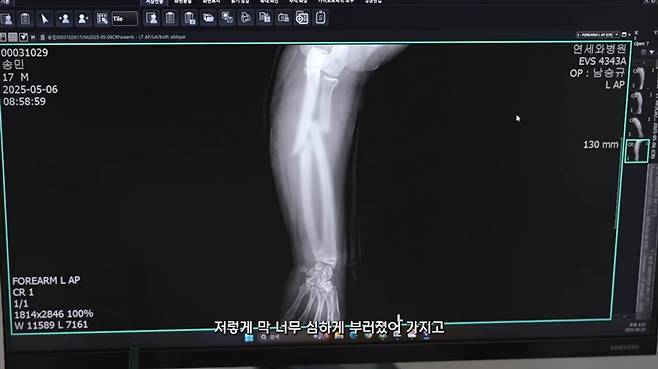

배우 오윤아가 발달장애를 앓고 있는 아들 송민 군의 팔 골절과 치료 과정을 공개했다.

영상 소개글에서 오윤아는 "오늘은 민이가 깁스를 푸는 날"이라며 입을 열었다. 그는 "팔이 부러졌다는 소식에 너무 놀랐는데 수술도 잘 끝나고 이제 깁스까지 푸니 마음이 조금 놓인다"며 걱정해준 팬들에게 감사를 전했다.

오윤아는 특히 이번에 가수 이정현의 남편이 운영하는 병원에서 큰 도움을 받았다고 밝혔다. "민이가 다쳤을 때 정말 정신이 없고 힘들었는데, 병원에 와서 상태를 바로 확인하고 신속하게 응급 수술을 받을 수 있었다"며 의료진에 대한 고마움을 표하기도 했다.

이어 오윤아는 "아들이 답답하니까 깁스한 팔로 벽을 치는데 그게 너무 재밌나 보더라. 결국 방 벽이 나가고 깁스를 세 번이나 다시 했다"고 말하며 양육의 어려움을 솔직하게 털어놨다. 현재는 상태가 많이 호전됐지만 깁스를 푼 후에도 민이는 당분간 반깁스를 착용해야 한다고 덧붙였다.

영상에서 담당 의사는 "전완부 골절이 있었따. 움직임이 많아 6주간 통깁스를 유지했다. 이제는 반깁스로 전환하지만,완전한 회복까지는 3개월 정도 더 주의가 필요하다"고 설명했다.